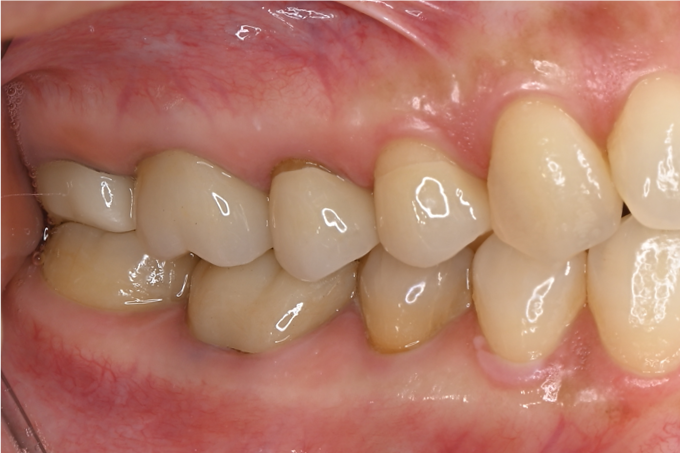

症例1

| 項目 | 詳細 |

|---|---|

| 患者様データ | 30代 女性 |

| 来院時の主訴 | 「右下の歯の治療後から違和感が続いている。」 |

| 医院の診断 | 虫歯の再発、慢性根尖性歯周炎、近心根パーフォレーション |

| 通院期間 | 6ヶ月 |

| 来院回数 | 8回(定期的なチェック含む) |

| 治療費 | 240,000円(税抜) 《内訳》 精密感染根管治療100,000円、ファイバーポストコア20,000円、セラミック治療120,000円 |

| リスクと副作用 | ①根管治療歯は長期的には破折するリスク ②メインテナンスが必要 |

| ココがこだわりのポイント☝ |

ラバーダム防湿とマイクロスコープを使用して丁寧に治療を行いました。 再根管治療のため、殺菌性があり歯を補強することのできる根管充填材料を使用しています。 |